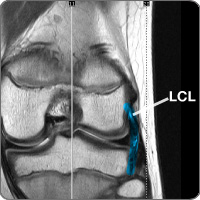

Lateral collateral ligament injury

cond-later-collaThe knee contains the lateral collateral ligament (LCL), one of four ligaments (tough band of tissue) connecting the femur (thigh) bone to the tibia (lower leg) bone. In combination with the medial collateral ligament (MCL), the ligament on the inside of the knee, the LCL lies on the lateral (outside) of the knee joint and provides stability to the knee for side-to-side movement. When the ligament is stretched beyond its normal range of movement, it can become sprained or torn. LCL injuries may involve other knee structures, such as the medial or lateral meniscus, which can present as pain on the opposite side (inside) of the knee. Other ligament tears can also occur, such as the posterior cruciate ligament (PCL), when the LCL is injured.